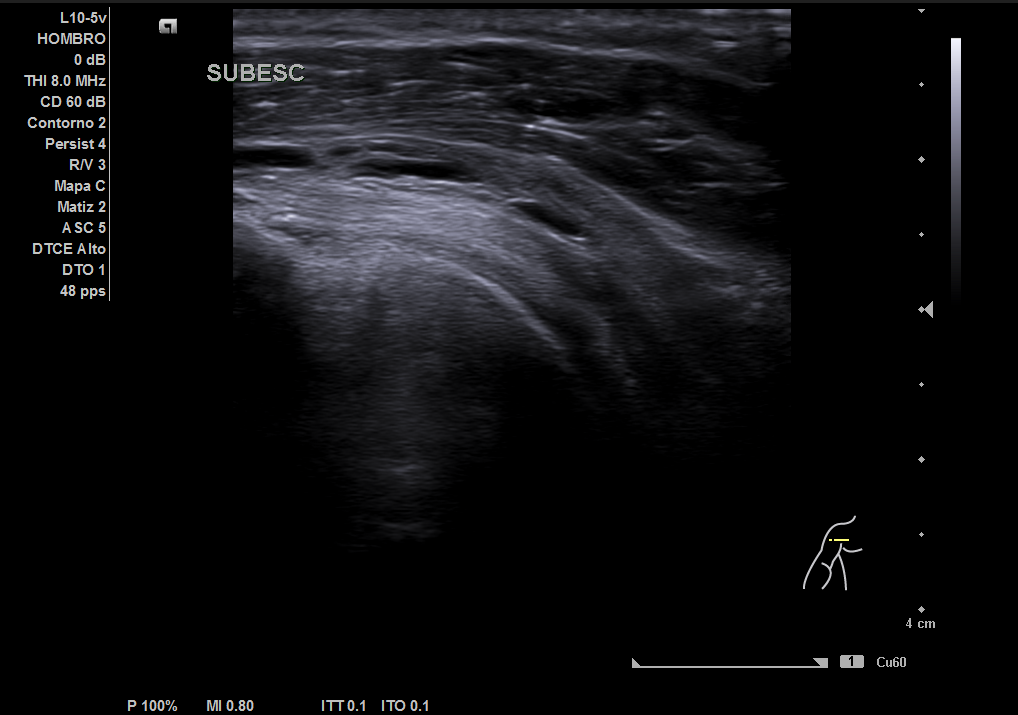

Descripción de los hallazgos ecográficos y las imágenes más relevantes para la resolución del caso

En la ecografía realizada observamos una rotura completa del tendón supraespino, rotura parcial del subescapular y severo derrame peritendón del bíceps junto con derrame articular glenohumeral.

Resonancia magnética: rotura completa del supraespinoso, rotura completa del subescapular, rotura miotendinosa del infraespinoso, severo derrame articular glenohumeral.